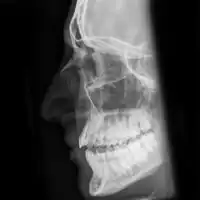

| Plain X-ray showing a nasal fracture | |

The most common causes include assault, trauma during sports, falls, and motor vehicle collisions.[1] Diagnosis is typically based on the signs and symptoms; with plain X-ray rarely of benefit.[1][6] CT scan may be useful if concerns of other fractures or complications are present.[6][4]

Nasal fractures are usually identified visually and through physical examination.[1] Medical imaging is generally not recommended.[1][2] A priority is to distinguish simple fractures limited to the nasal bones (Type 1) from fractures that also involve other facial bones and/or the nasal septum (Types 2 and 3). In simple Type 1 fractures X-Rays supply surprisingly little information beyond clinical examination. However, diagnosis may be confirmed with X-rays or CT scans, and these are required if other facial injuries are suspected.[2]

Nasal bone fracture